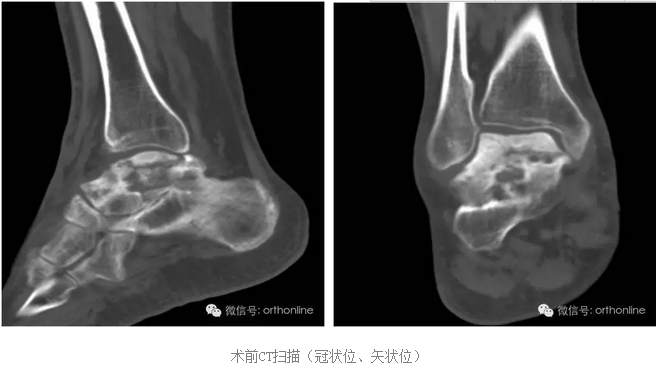

世界上首例3D打印的具有生物学功能的个性化假体治疗距骨塌陷性坏死在重庆获得成功

创伤引起的距骨塌陷性坏死一直是医学界面临的难题,治疗手段非常有限,目前只能采用以牺牲踝关节生物学功能的胫-距-跟植骨融合来缓解病人的痛苦,严重影响患者生活质量。

针对上述问题,由第三军医大学西南医院唐康来教授牵头,中国科学院重庆绿色智能技术研究院、物质结构研究所、金属研究所、化学研究所、理化技术研究所等十个单位协作攻关,分别从3D打印设备与专用材料、个体性产品开发与临床应用方面进行研究,研制了世界上首个3D打印的具有生物学功能的个性化距骨假体,于2016年7月4日在重庆第三军医大学西南医院成功应用于创伤引起的距骨塌陷性坏死病例。